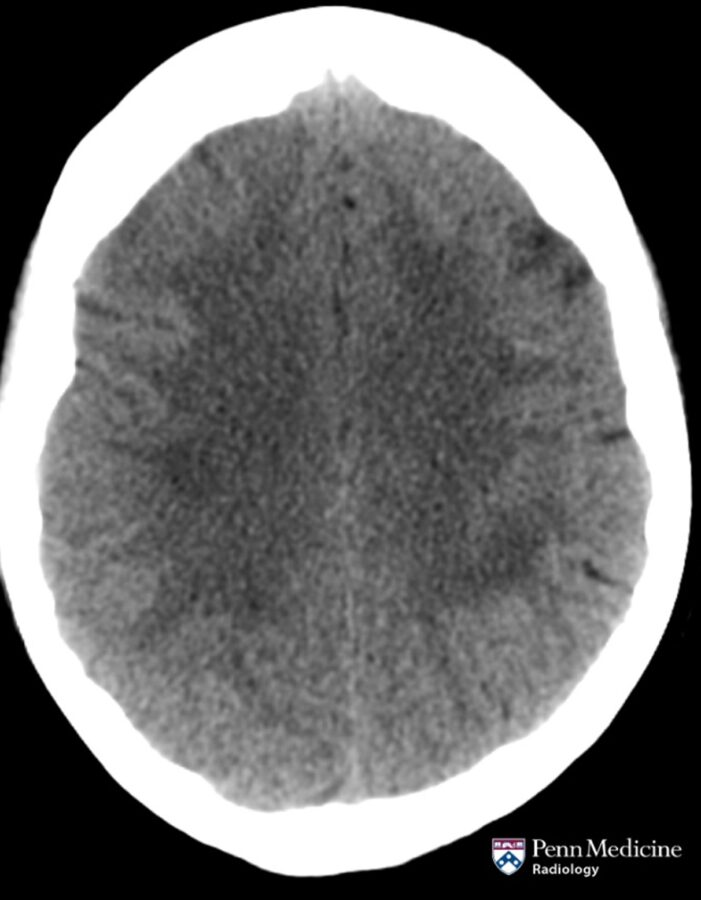

60-year-old woman with weight loss, fevers, confusion

A 60-year-old woman with history of treated pulmonary adenocarcinoma and renal and pancreas transplantation on chronic immunosuppression presents with progressive weight loss, fevers, and confusion.

Published Date: February 26, 2026

Tags:

Brain

,

CT

MRI

Neuroradiology